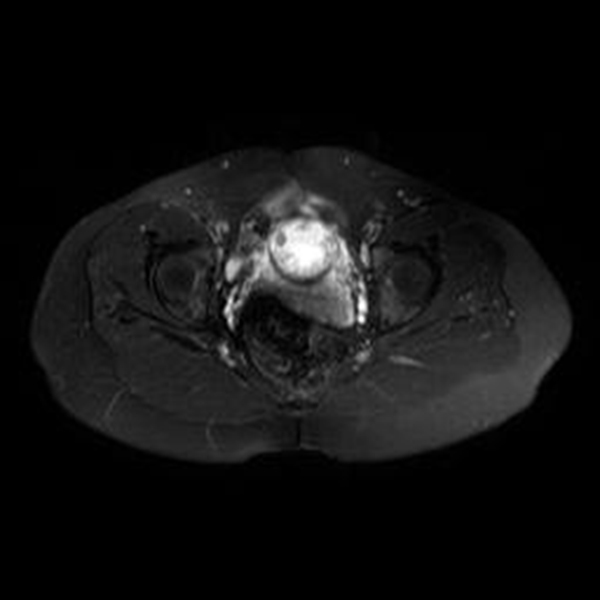

A la paciente se le realizó una prueba en sangre para cuantificar la fracción beta de la gonadotrofina coriónica humana (Abbott Laboratories. Architect.B-hCG Total), que se reportó en 31.819 mUI/ml. También se le tomó una ecografía endovaginal (Toshiba-Xario XG) que mostró la presencia de útero con medidas de 72 × 52 × 54 mm con un cuello de 35 mm con orificio interno cerrado. El endometrio midió 18 mm, sin evidencia de saco gestacional intrauterino y en la región ístmica y cervical, por debajo de las arterias uterinas, se encontró un saco gestacional de 30 mm con presencia de embrión único de 20,6 mm sin presencia de actividad cardiaca fetal (figuras 1 a 4).

Se realizó una RNM (Philips 1.5 Tesla) que permitió confirmar el diagnóstico de EEC (figuras 5 a 8).